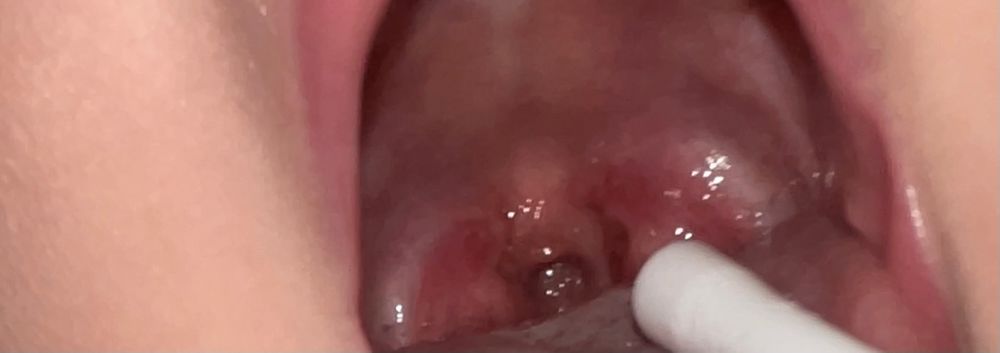

Ребёнок 1,9 лет .Скажите, это считается красное горло? Неделю назад была температура сутки, больше никаких симптомов, пришла врач сказала зубы. Я смотрю сама горло мне кажется красное. С тех пор зубы не вылезли новые, горло всё такое же, не пойму надо лечить вызывать чтоб назначили от горла?

Цвет горла лечить не нужно. Если нет температуры, ребенока ничего не беспокоит - даже смысла показывать врачу нет.